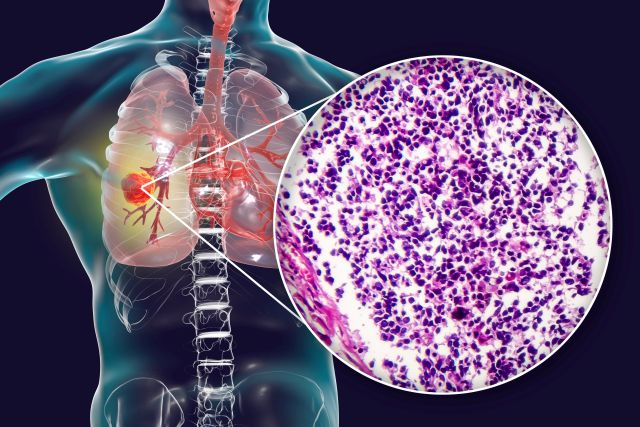

🔒 Fortgeschrittenes NSCLC: Atezolizumab bleibt Standard in der Erstlinie

Fortgeschrittenes NSCLC: Datopotamab-Deruxtecan plus Pembrolizumab zeigt vielversprechende Wirkung in der Erstlinie

🔒 Neueinführung: Serplulimab beim kleinzelligen Lungenkarzinom

🔒 Was ist neu: Die Leitlinie NSCLC

🔒 Aktuelle Therapieoptionen bei SCLC

🔒 ALK+ NSCLC: In der Erstlinie auf Lorlatinib setzen

🔒 ES-SCLC: Erster Anti-PD-1-Antikörper erhält Zulassung